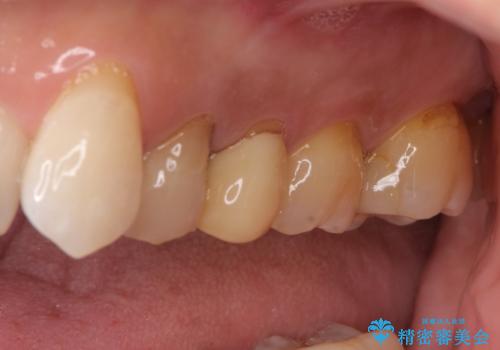

根管治療について

保険根管治療は回数がかかることが多く、終了予定がわかりにくいです。

当院では、根管治療は長い時間のご予約を頂き、多くの場合2~3回で終わります。

根管治療は歯内の治療なので患者様には見えない場所ですが、ここが細菌で汚染されると激しい痛みや長引く違和感の原因になります。

当院では、清潔な治療を徹底し、顕微鏡を使用した精密な治療を行っています。

症状や根管の状態により、治療金額が異なります(5~10万円目安)。治療回数による費用負担の増減はありません。